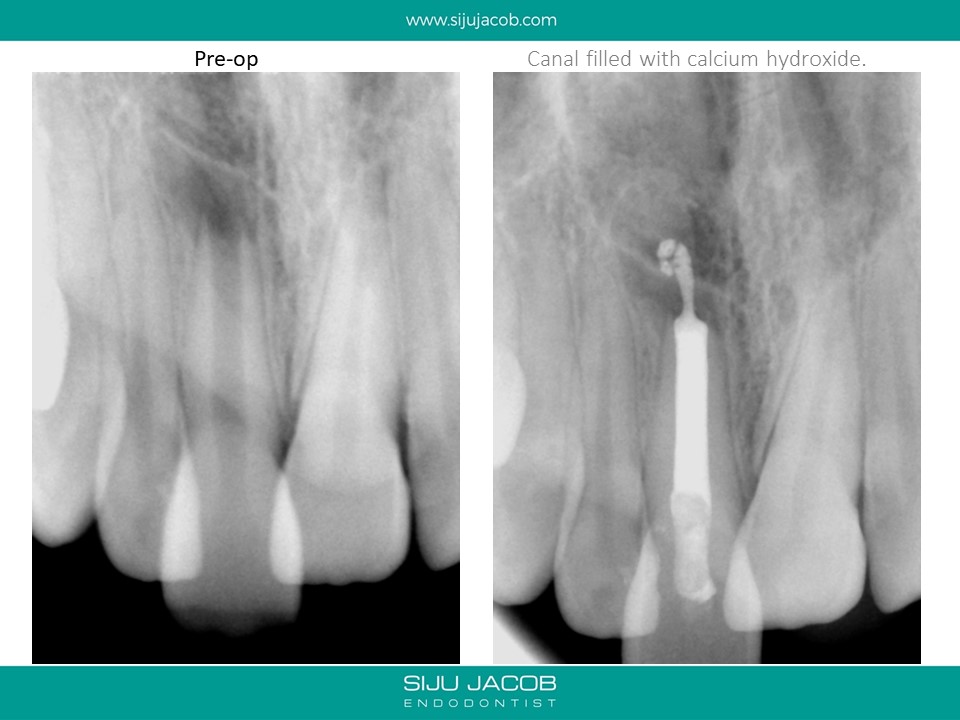

This was one of the first apexification cases i did. I started this case before i purchased a microscope (and I wasn’t using MTA at that time). I packed the canal with a thick Iodoform + Calcium hydroxide (Metapex). By the time the patient came back after a year, I had a microscope and it was fascinating to Microscopically observe the apical barrier that had formed.